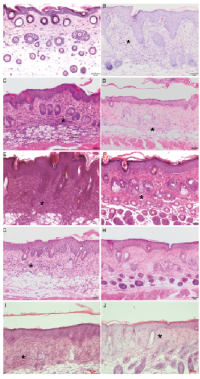

In the skin of mice treated topically with soft cream, no lymphocytic infiltration was visible, whereas mice treated with IMQ showed a marked dermal infiltration of lymphocytic cells (Fig. 4A, B). In the skin of mice treated with the H2R agonist amthamine plus IMQ, lymphocytes persisted in the dermal layer, but the infiltration appeared to be less severe than in mice treated with vehicle plus IMQ (Fig. 4C, E). In the skin of mice treated with the combination of amthamine and JNJ-39758979 plus IMQ, lymphocytic infiltration of the dermis could only rarely be detected (Fig. 4H), whereas in the corresponding vehicle group a marked lymphocytic infiltration was again visible (Fig. 4G). In H4R–/– mice, lymphocytes persisted in the dermal layer, but infiltration appeared to be less severe than in wild-type mice (Fig. 4I, J).

Fig. 4. Imiquimod (IMQ)-induced dermal lymphocytic cell infiltrates. Representative histological pictures of lymphocytic cell infiltrates (asterisks) in the dermis. The treatment of mice using a combination of JNJ-39758979 and amthamine reduced lymphocytic cell infiltrates (asterisks) in the dermis. Skin of mice was treated topically with (A) soft cream or (B–J) IMQ for 10 consecutive days. (A) Skin of mice treated topically with soft cream. No lymphocytic infiltration (score (–)) was visible. (B) Skin of mice treated with IMQ topically. Lymphocytic infiltration (++++) is visible. (C, E, G) Skin of mice treated with vehicle administered intraperitoneally (i.p.) + IMQ topically. Lymphocytes (++++) persisted in the dermal layer (asterisks). (D) Skin of a mouse treated with amthamine i.p. + IMQ topically. Lymphocytes (+++) persisted in the dermal layer (asterisks), but infiltration appeared to be less severe than in mice treated with vehicle i.p. + IMQ topically (C). (F) Skin of a mouse treated with JNJ-39758979 i.p. + IMQ topically. Lymphocytes (+++) persisted in the dermal layer (asterisks), but infiltration appeared to be less severe than in mice treated with vehicle i.p. + IMQ topically (E). (H) Skin of a mouse treated with amthamine + JNJ-39758979 i.p. + IMQ topically. Lymphocytic infiltration (+) of the dermis could only rarely be detected. All drugs were given in a dosage of 20 mg/kg i.p. twice daily and were compared with treatment with vehicle (aqua ad injectionem, twice daily i.p.). (I) Skin of a wild-type mouse treated with IMQ topically. Lymphocytes (++++) persisted in the dermal layer (asterisks), infiltration appeared to be more severe than in H4R–/– mice (+++, J). Bars represent 50 µm.